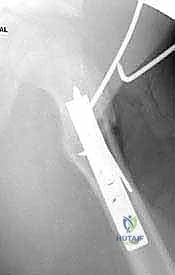

- الأشعة السينية الرقمية (Digital X-Rays): أخذ صور بوضعيات متعددة (أمامي خلفي، وضعية الضفدع) لقياس "زاوية عنق الفخذ-الجذع" بدقة متناهية، وحساب نسبة التغطية الحُقية.

يتم وضع المريض على طاولة عمليات خاصة (Fracture Table) تسمح باستخدام جهاز الأشعة السينية الفلوروسكوبي (C-arm) أثناء الجراحة لمراقبة كل خطوة بشكل مباشر.

3. إدخال سلك الدليل (Guide Wire Placement)

هذه هي الخطوة الأكثر أهمية. باستخدام الأشعة المباشرة، يقوم الدكتور بإدخال سلك معدني رفيع في عنق عظم الفخذ باتجاه الرأس. يتم وضع هذا السلك بزاوية محسوبة مسبقاً بدقة متناهية لتتطابق مع زاوية الشريحة (90 درجة).

5. قطع العظم (The Osteotomy)

باستخدام منشار جراحي عالي الدقة، يقوم الدكتور هطيف بقطع عظم الفخذ أسفل منطقة المدور الكبير (Subtrochanteric). في هذه المرحلة، يتم إزالة إسفين عظمي صغير (Wedge) بالزاوية المطلوبة لتصحيح التشوه.